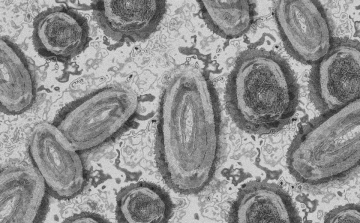

Egy 3 év alatti gyermek fertőződött meg majomhimlővel Belgiumban

Belgiumban egy 3 év alatti gyermek fertőződött meg majomhimlővel - számolt be róla szerdán a Sudinfo hírportál.